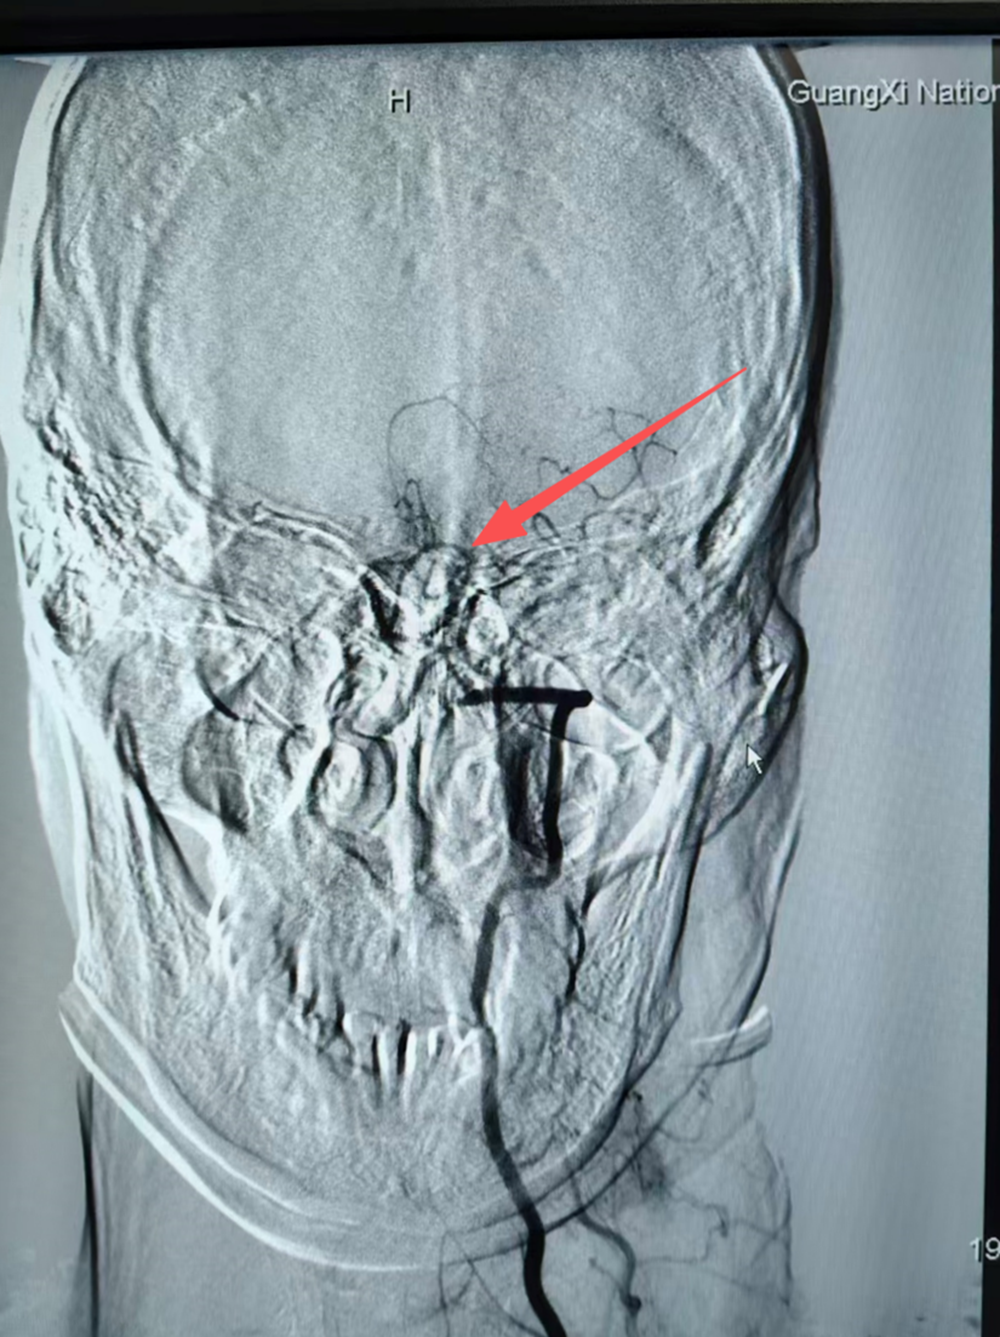

手术当天,气氛凝重。在DSA的引导下发现:患者右侧椎动脉发育不良,左侧椎动脉V4段呈长节段细丝样狭窄,基底动脉、大脑后动脉未显示。主刀乔振虎副主任手持一根细如发丝的微导丝,送入颅内球囊,开始了一场“毫米级”的跋涉,逐步扩张患者纤细的血管。血管路径异常迂曲,且伴有动脉粥样硬化斑块,这要求术者的操作必须兼具极高的精准性与极致的稳定性,每一步的导丝和球囊推进、每一次的“冒烟”造影确认位置,都是在为后续的血管再通铺平道路,同时要极力避免栓子逃逸、血管夹层或穿支动脉闭塞等严重并发症。

屏幕上,是错综复杂的血管网络。神经内科五区神经介入手术团队手中,是生命的全部重量,也是一个家庭的未来。时间在寂静中流淌,当那根承载着希望的微小球囊导管,在导丝的精准引导下,穿越迂曲的路径,终于抵达堵塞最严重的“隘口”时,手术进入了最关键阶段。

球囊被缓慢、精确地充盈,以恰到好处的压力扩张狭窄的血管壁。瞬间,屏幕上消失的血流信号重新开始跳跃、奔腾,如同枯竭的河床重新迎来了生命的溪流。“通了!”这一刻的静默,比任何掌声都更有分量。这不仅意味着一次血管内介入治疗的技术成功,更为一个家庭的期望,凿开了第一道切实的光芒。